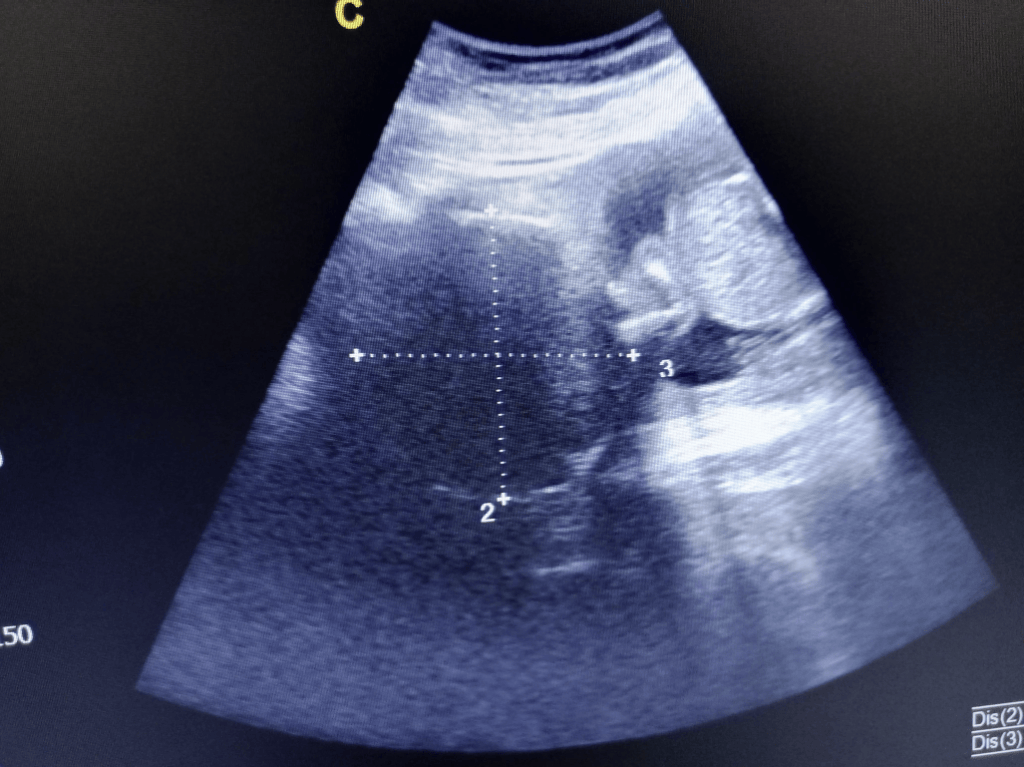

Pretpostavka o prisustvu mioma postavlja se na osnovu simptoma i ginekološkog pregleda, kada se može napipati uvećana materica. Definitivna dijagnoza i praćenje se vrši ultrazvučnim pregledom, najčešće vaginalnom sondom. Veliki miomi mogu zahtevati i abdominalni ultrazvuk.